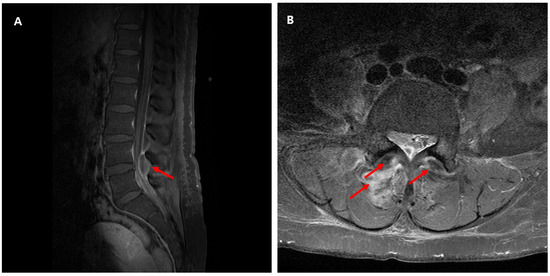

Background: Nocardia are a group of bacteria known to cause pulmonary, cutaneous, neurologic, or disseminated diseases, usually in immunocompromised hosts. Within the Nocardia family is Nocardia transvalensis, a rarely encountered and underreported organism in the clinical literature. Case: Here, we report the case of an immunocompetent patient presenting with lumbar pain diagnosed and treated for disseminated Nocardia transvalensis infection. Our patient underwent magnetic resonance imaging (MRI), demonstrating possible abscess and subtle osteomyelitis of the L3-L4 facet joint and transverse process; a subsequent biopsy and culture resulted in Nocardia transvalensis. Further imaging with a computed tomography (CT) scan of the head revealed a 9 mm enhancing supratentorial lesion. The patient was treated with empiric antibiotics, but this was narrowed to levofloxacin, linezolid, and trimethoprim-sulfamethoxazole after antibiotic sensitivities cropped up. Conclusions: Within this case, we extensively discuss the clinical pathogenesis of Nocardia transvalensis in an unusual host, the diagnostic approach to confirming active Nocardia infection, and the susceptibility patterns in a relatively unstudied organism. Full article

Figure 1